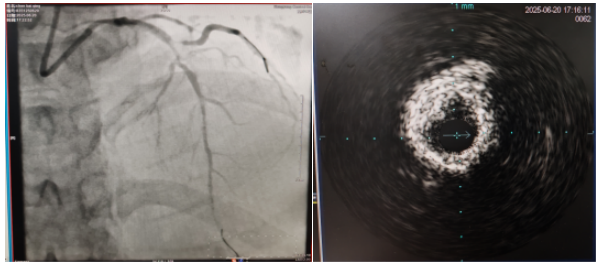

術(shù)中,趙慶禧主任醫(yī)師、雷剛副主任醫(yī)師運用IVUS血管內(nèi)超聲技術(shù)評估,發(fā)現(xiàn)患者前降支、對角支0.1.1型真性分叉病變,前降支近中段嚴(yán)重鈣化、成角并99%狹窄,對角支近段嚴(yán)重鈣化并99%狹窄,傳統(tǒng)冠狀動脈旋磨術(shù)容易引起冠狀動脈穿孔,決定采用沖擊波球囊技術(shù)即血管內(nèi)沖擊波鈣化碎裂術(shù)對患者嚴(yán)重鈣化的血管進行介入治療。通過球囊低壓擴張,向血管病變處發(fā)射非聚焦、低能量、脈沖式的沖擊波,對前降支及對角支進行了連續(xù)5個周期沖擊波脈沖治療,安全地碎裂淺、深層鈣化,原本看似堅不可摧的環(huán)形鈣化區(qū)逐漸顯現(xiàn)出了裂痕,多處關(guān)鍵位置發(fā)生了斷裂,充分預(yù)處理后于前降支近中段串聯(lián)植入支架3枚,對角支植入藥物球囊,術(shù)后造影見血管病變處狹窄完全消失,支架膨脹完全,貼壁良好,各項生命體征平穩(wěn),手術(shù)非常成功,患者返回心血管內(nèi)科病房繼續(xù)治療,并于4天后順利出院。